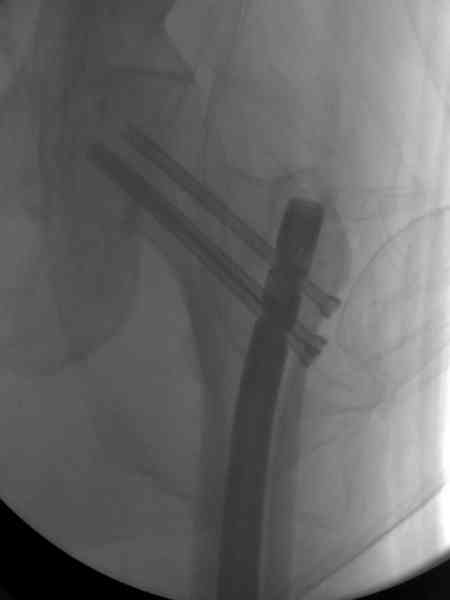

Здесь представлены снимки больного 65 лет, поступившего с диагнозом перелом

бедра после автоаварии.

В первый же день произведено антеградное штифтованием DePuy Trochanteric Nail.

На второй день (7) обнаружен пропущенный перелом,

сделаны Компьютерная Томограмма

и проведены шурурпы через и спереди штифта без удаления.

Послеоперационные снимки